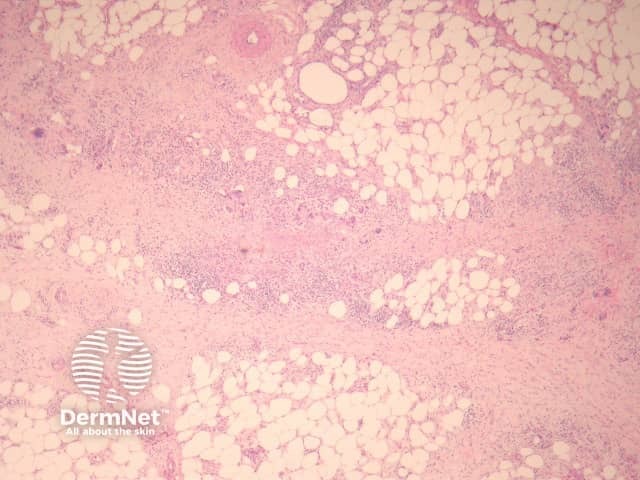

Erythema nodosum histologically represents the prototype of a septal panniculitis. The classic histopathologic presentation of erythema nodosum is that of a septal panniculitis with a mixed cellular infiltrate of lymphocytes, histiocytes, giant cells, and occasional eosinophils and a characteristic absence of vasculitis (figures 1-3).

Figure 1